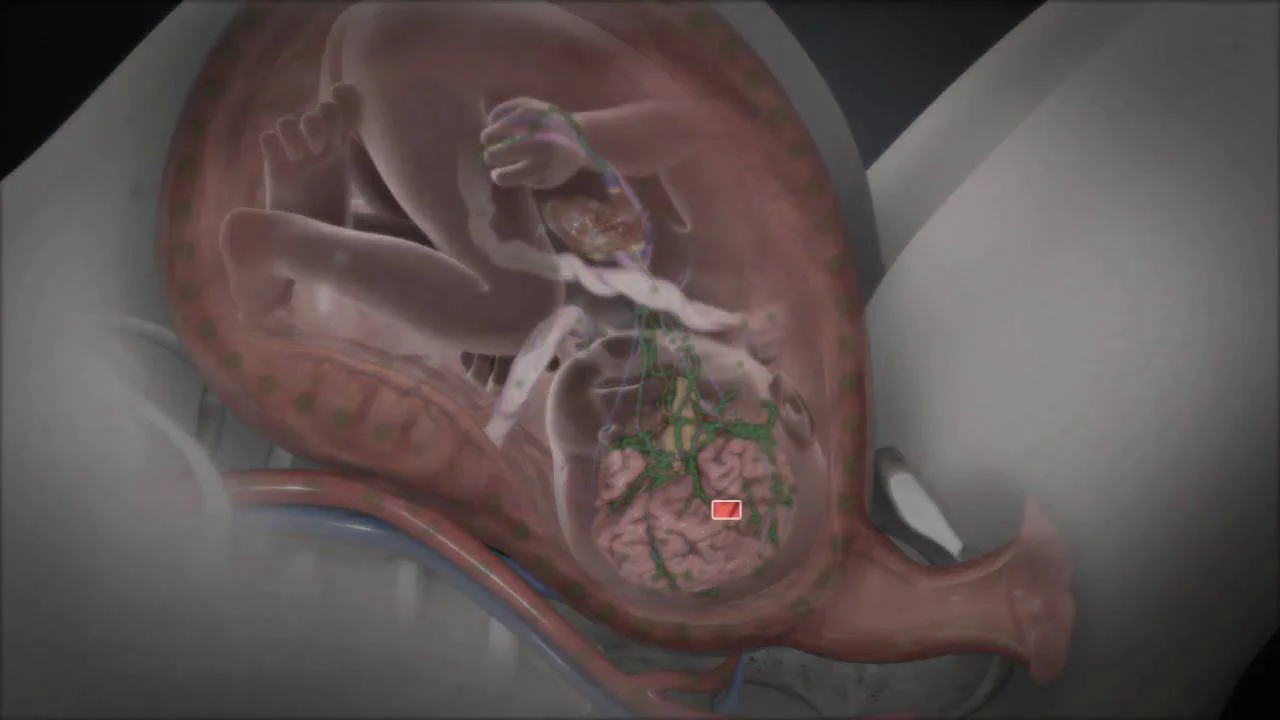

Much less commonly, you can transmit the virus if you’re having a recurrent infection. If you’ve ever had a herpes outbreak, the virus remains in your body and can become reactivated. In rare cases, a pregnant woman may transmit the infection to her baby through the placenta if she gets herpes for the first time in her first trimester. If a baby is infected this way, the virus can cause a miscarriage or serious birth defects.

If you’re having an outbreak or symptoms of an impending outbreak when your water breaks or when you go into labor, you’ll need an immediate cesarean delivery. This would be the case if you have any visible sores on your cervix, vagina, or external genitals, or any symptoms, like tingling, burning, or pain, that sometimes signal an imminent outbreak. (Currently, there’s no quick and reliable way to test whether you’re actually shedding virus.)

To improve your chances of being able to deliver vaginally, most experts — including the American College of Obstetricians and Gynecologists — recommend that pregnant women with recurrent genital herpes be offered oral antiviral medication from 36 weeks or so until delivery. Recent studies show that this reduces the risk of an outbreak at the time of labor.